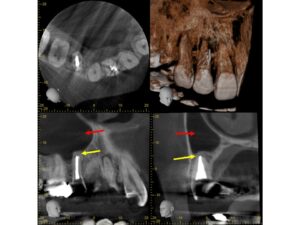

初診時CT画像。根管充填が不十分で、根尖部に根尖病巣による黒いCT透過像を認める(黄色矢印)。上顎洞は上方まで白い不透過性を呈し、上顎洞全体に炎症所見を認めている(赤矢印)。歯が原因となっている典型的な歯性上顎洞炎であると診断し、感染根管治療を行うこととした。

根管充填後CT画像。根尖部のCT透過像は完全に消失して歯槽骨の再生を認める(黄色矢印)。上顎洞の内部は炎症が消失し、正常な黒い含気腔を呈している(赤矢印)。術前の症状はすべて完全に治癒した。